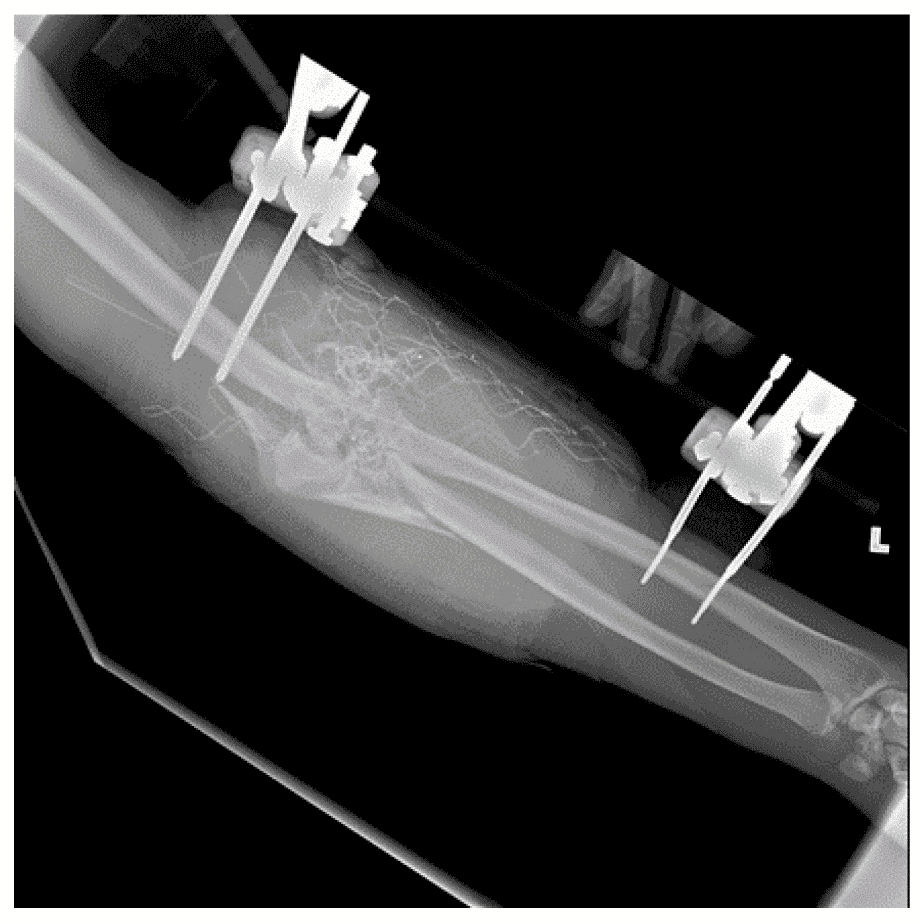

Зображення 5. Використання апарата зовнішньої фіксації для стабілізації нижньої кінцівки після вибухової травми

На базовій рентгенограмі, отриманій перед процедурою, видно осколкові переломи у дистальній третині стегнової кістки та середній ділянці тіла великогомілкової кістки. Над колінним суглобом було розташовано апарат зовнішньої фіксації, тоді як розширений зовнішній фіксатор у вигляді «дельтоподібної рами» використовує замок стержня у проксимальній ділянці великогомілкової кістки для стабілізації сегментарного перелому великогомілкової кістки.

Зобр. 5c. Зовнішній фіксатор

Зобр. 5d. Зовнішній фіксатор з дельтоподібною рамою